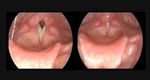

Exercise Induced Laryngeal Obstruction (EILO)

   Paradoxical closure of vocal cords

during inspiration.

 Also  referred to as vocal cord dysfunction

(VCD)

   EILO more accurate term

   Frequently misdiagnosed as EIB

 Up   to 25% of those referred for EIB

EILO Presentation and Diagnosis

Normal              EILO

   Intermittent shortness of breath

   Voice changes, stridor, cough

Expiration

   Usually harder to get air out

   Usually improves after cessation of

activity (as opposed to EIB)

   May be linked to environmental triggers

   Link to stress and anxiety                                               Decreased Flow

During Inspiration

Inspiration

   Diagnosis: spirometry, laryngoscopy